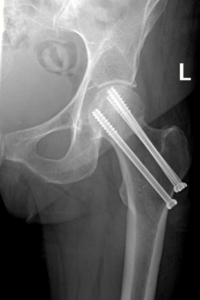

Femoral neck fractures occur when there is a break in the segment of bone that connects the thigh bone to the femoral head (Figure 1a). The femoral head is the “ball” portion of the hip joint which makes up the ball and socket of the joint. When the ball shifts out of place as a result of this fracture in an elderly individual, the treatment is often a form of hip replacement surgery (Figure 1b). When the ball has not shifted significantly, screws are often inserted to fix the bone in place (sometimes referred to as a pinning procedure, Figure 1c).